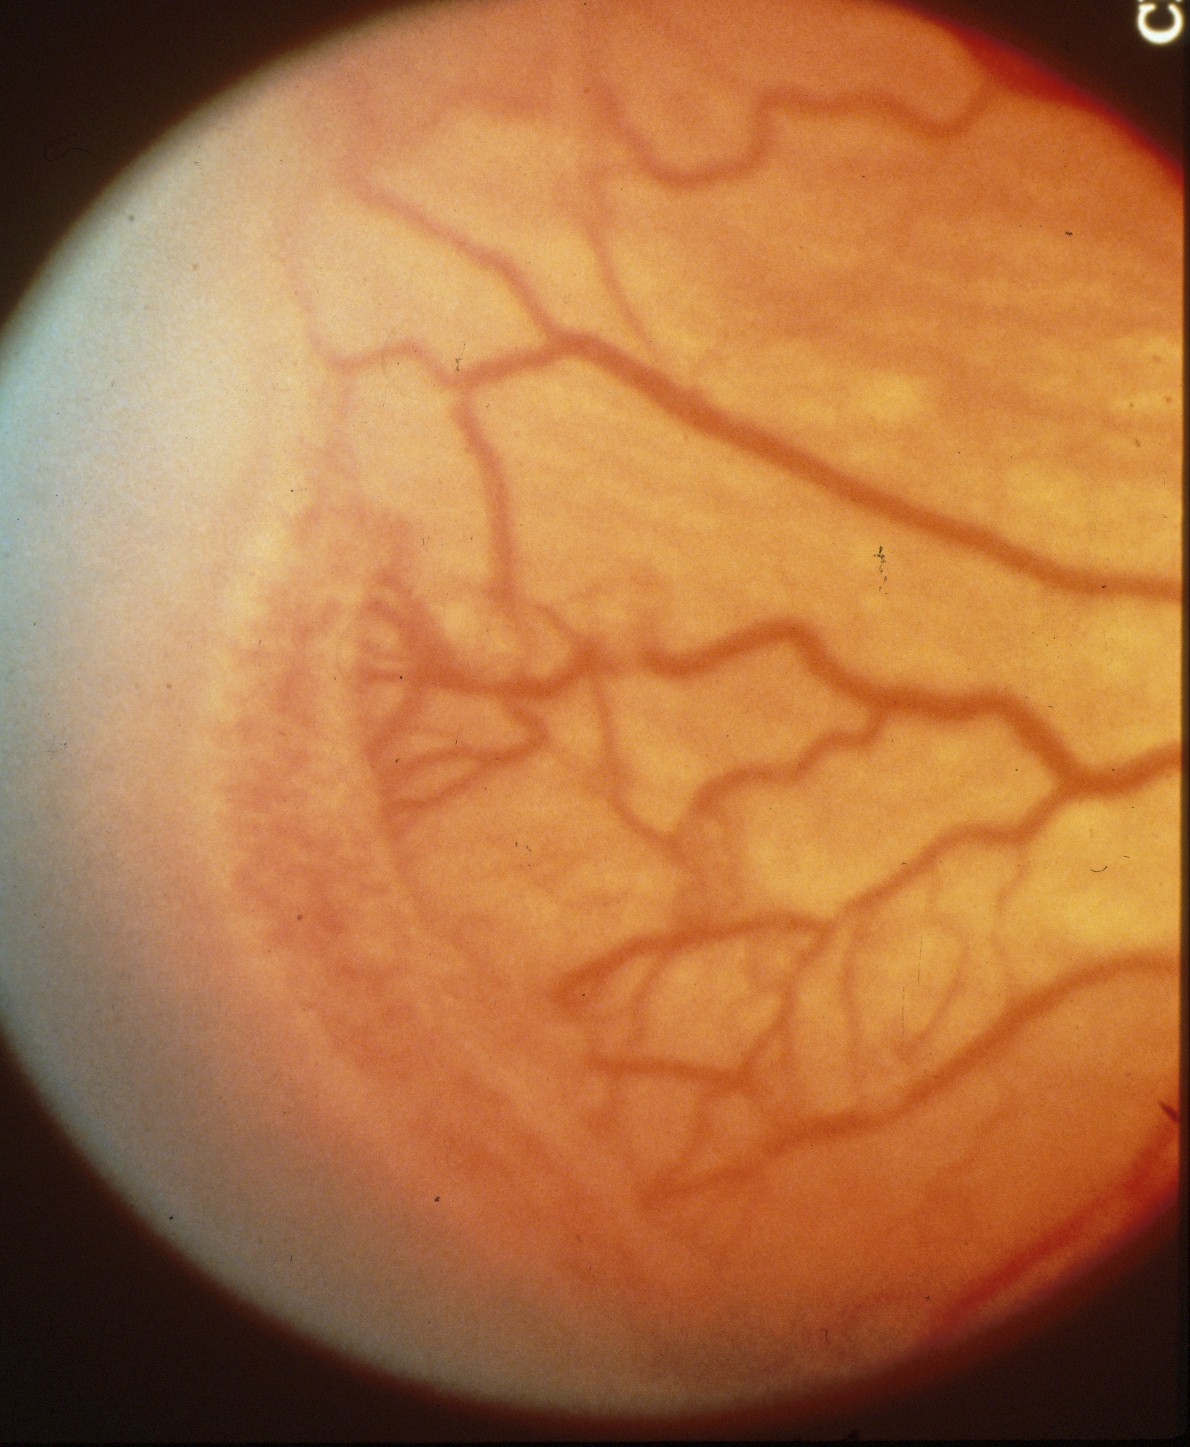

When infants are born prematurely the blood vessels in the retina (inner most layer of the eye) have not completed their development. In certain infants these blood vessels can grow abnormally once the baby is outside of the womb.

There are multiple stages of abnormal blood vessel growth, the most severe of which can lead to significant vision loss.